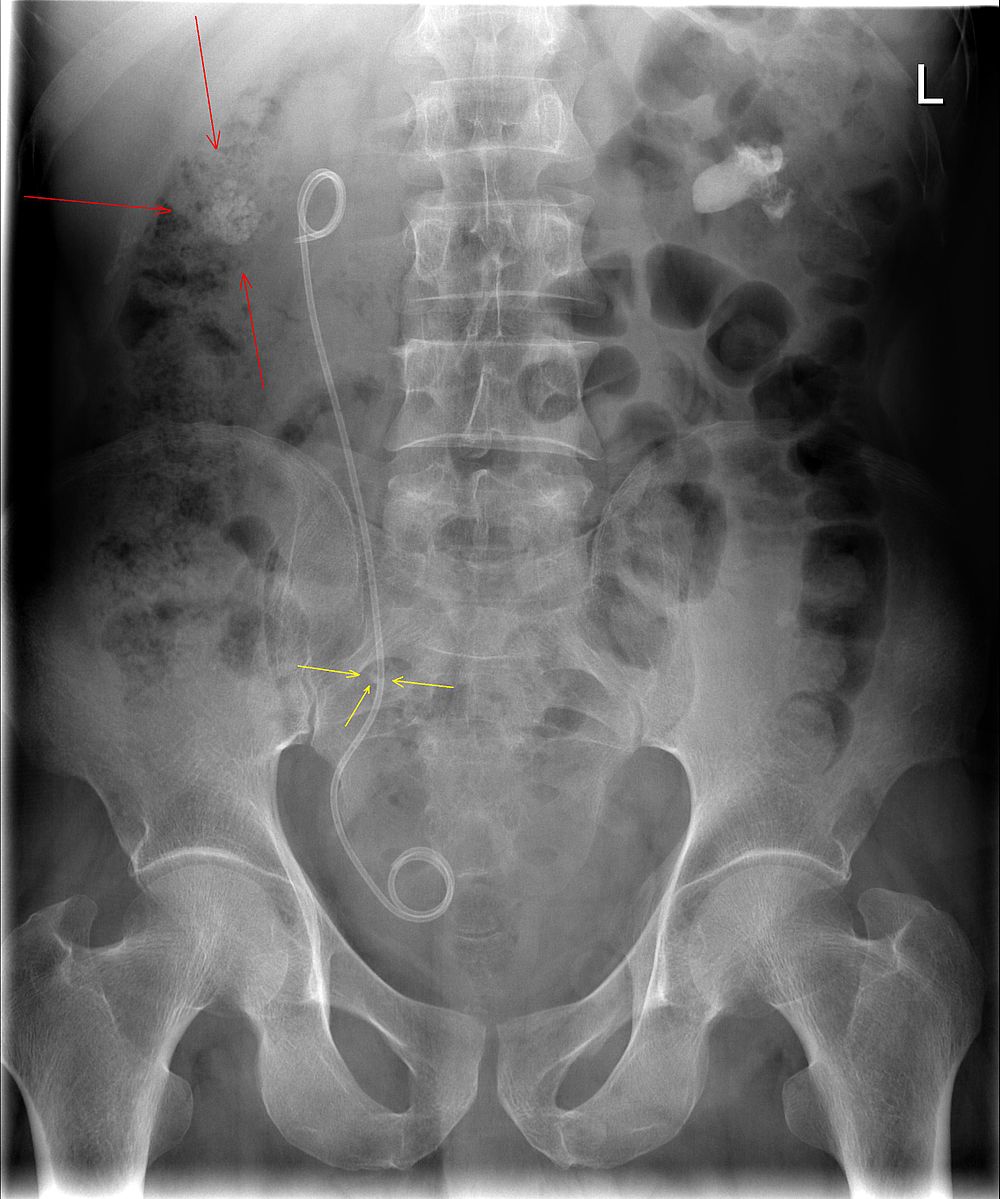

“On initial inspection, there is a ureteric stent in situ in the right ureter, but I will proceed to go through it systematically.”

B – Looking at the film, the small bowel is visible but it is not dilated. There is evidence of some faecal loading in the ascending colon. No evidence of bowel obstruction.

O – Looking at the other organs, there is no basal lung consolidation. No hepatobiliary abnormality. There is evidence of calcification in the right and left kidneys as well as a possible stone in the right ureter.

B – There are no fractures to the bones. There is a lateral curvature of the spine but the vertebrae appear normal. There is normal spacing of the sacroliliac and hip joints.

C– There are bilateral calcifications in the kidneys.

In summary this AXR shows some faecal loading in the ascending colon, bilateral calcifications in the kidneys and a right sided ureteric stent in situ.

Right sided ureteric Stent